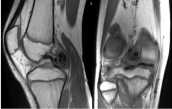

These images prompted the treating surgeon to order an MRI without contrast to further characterize the mass (Figure 8 and Figure 9). The differential diagnosis following MRI included synovial chondromatosis, atypical pigmented villonodular synovitis, or a large chondral loose body.

Figure 8: Coronal and sagittal T1 MRI images of right knee. View Figure 8

Figure 9: Axial, coronal, and sagittal T2 fat saturated images of right knee.

The MRI shows a 3.9 × 1.6 × 2.9 low T1 and low T2 weighted mass in the posterior joint space that appeared intimately associated with the meniscofemoral ligament of Wrisberg. View Figure 9